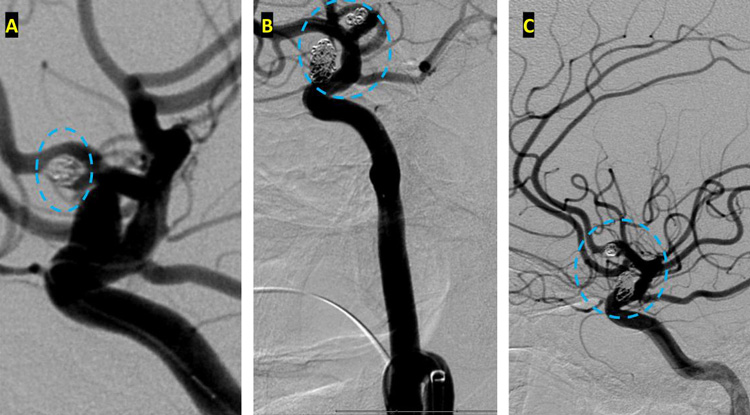

On admission, she presented as a GCS 3, was intubated, and stabilized hemodynamically in preparation for emergent catheter cerebral angiography, which revealed 2 discrete geographically located aneurysms – 1) Anterior Communicating and 2) Right ICA Supra-Clinoid Segment. (Figure 2.)

The Pattern of Hemorrhage was diffuse and generalized. On more careful analysis, however, there appeared to be focal hemorrhagic clot within the anterior inter-hemispheric fissure which raised greater suspicion for the Anterior Communicating Aneurysm as the source of hemorrhage. Although Acom Aneurysm was smaller, it’s irregular shape and eccentric “nipple” suggested potential rupture point. (Figure 3.)